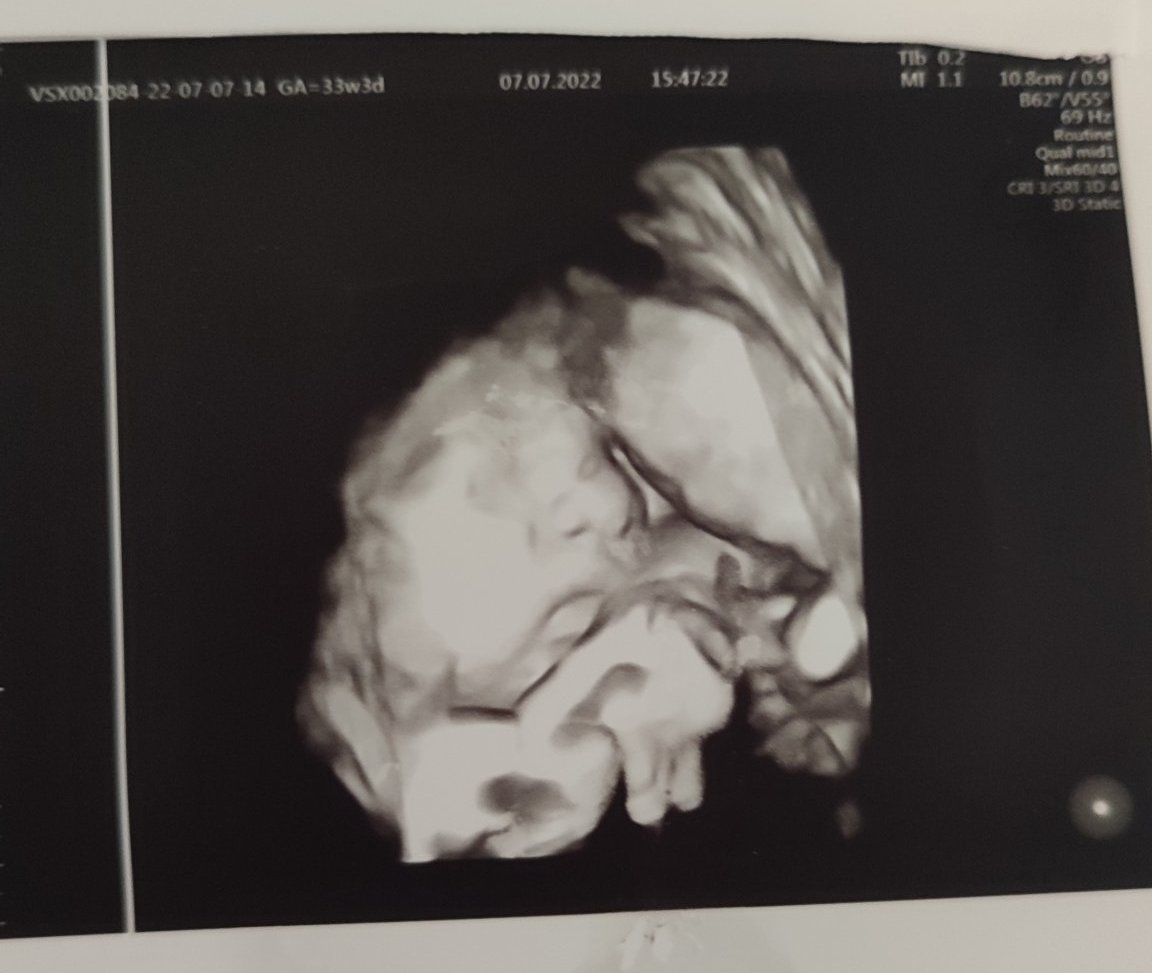

А ето я и бебка от прегледа в Токуда:

Главичката и е в плацентата и очичките не се виждат, но поне устенца, бузки и носле се виждат 🥰